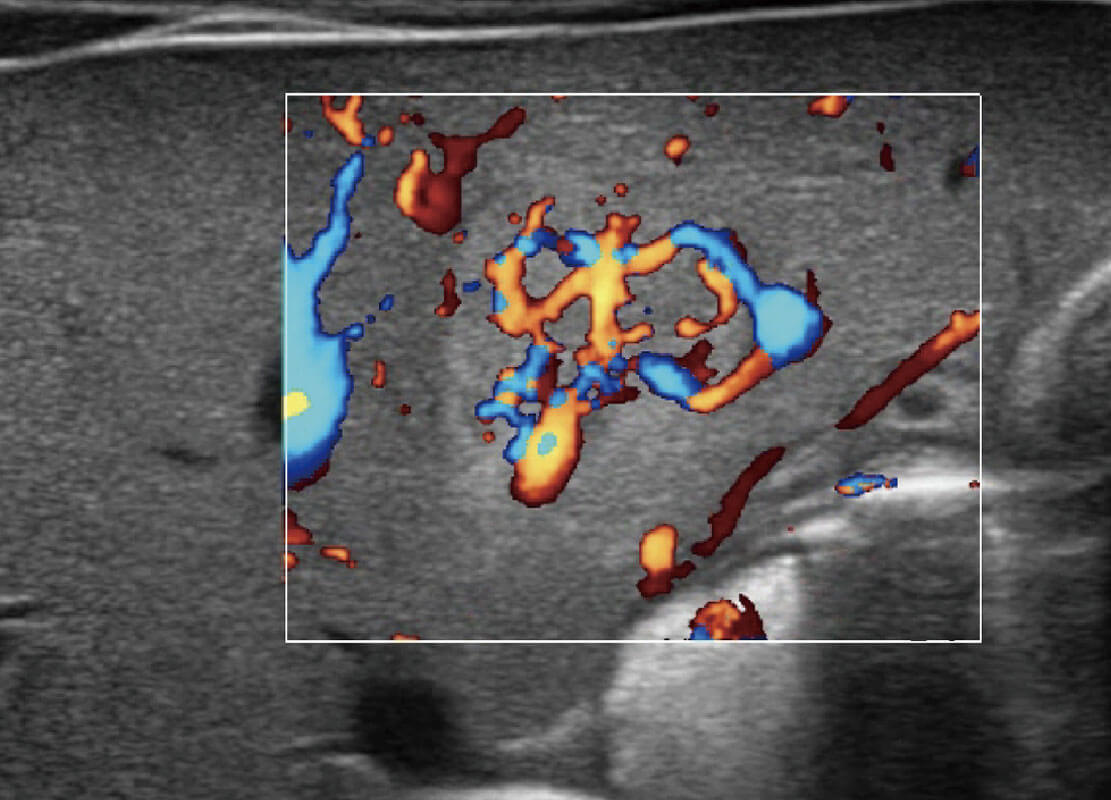

P60搭载宽频带线阵探头、宽景成像、弹性成像技术,为您提供乳腺应用方案。P60支持高频相控阵探头、线阵探头、腹部高频探头、腹部微凸探头等,丰富的探头群搭载敏感的彩色血流成像,适用于新生儿多种脏器检测要求,满足新生儿筛查需求。

乳腺导管癌

乳腺癌显微血流

新生儿肝血管癌

新生儿脊髓圆锥

新生儿心脏